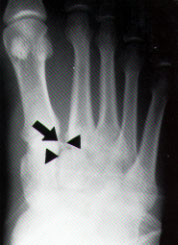

• widening of the interval between the 1st and 2nd ray

• seen on AP view

• may see bony fragment (fleck sign) in 1st intermetatarsal space

• represents avulsion of Lisfranc ligament from base of 2nd metatarsal

• diagnostic of Lisfranc injury

5th metatarsal base fracture

• Classification

Zone 1

(pseudo Jones fx)

• Proximal tubercle (rarely enters 5th tarsometatarsal joint)

• Due to long plantar ligament, lateral band of the plantar fascia, or contraction of the peroneus brevis

• Nonunions uncommon

Zone 2

(Jones fx)

• Metaphyseal-diaphyseal junction

• Involves the 4th-5th metatarsal articulation

• Vascular watershed area

• Acute injury

• Increased risk of nonunion (15-30%)